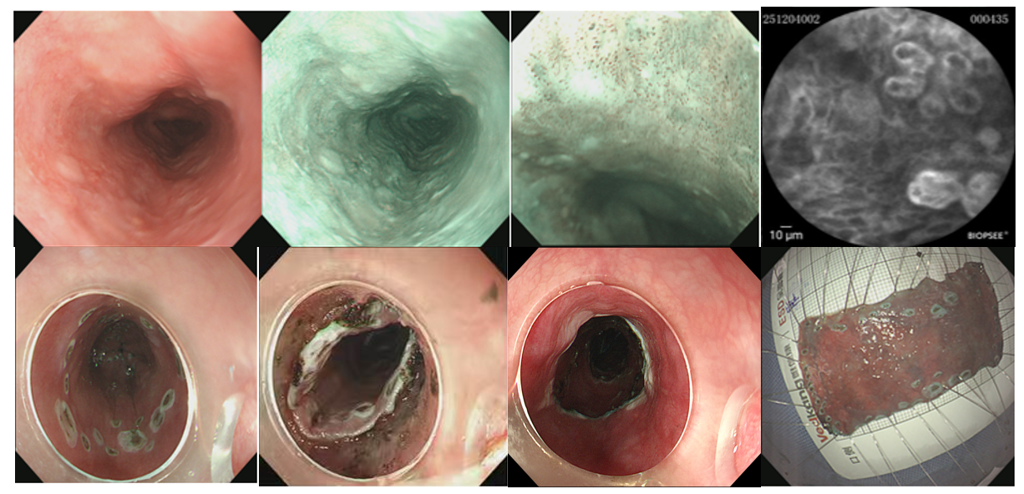

庞慧芳团队在ESD术前借助共聚焦激光显微内镜联合放大内镜碘染色精查,明确病灶性质及范围后,先剥离食管下段病变,再对中段病变实施环周剥离,完整切除两处肿瘤。术后病理回报提示:食管中段高级别鳞状上皮内瘤变,局灶早期中分化鳞状细胞癌,癌浸润深度位于黏膜固有层,未侵及黏膜肌层,未见脉管内癌栓及神经侵犯,水平及垂直切缘均净;食管下段为低级别鳞状上皮内瘤变,水平及垂直切缘干净,达到治愈性切除。患者术中出血量约15ml,术后恢复良好,无出血及穿孔等并发症,术后第3天开始进流食,嘱其定期复查胃镜,如出现狭窄,定期进行扩张及激素口服预防狭窄治疗,确保长期疗效与生活质量。

食管中段全周型早期食管癌(距门齿30-34cm)

食管下段低级别鳞状上皮内瘤变(距门齿37-39cm)